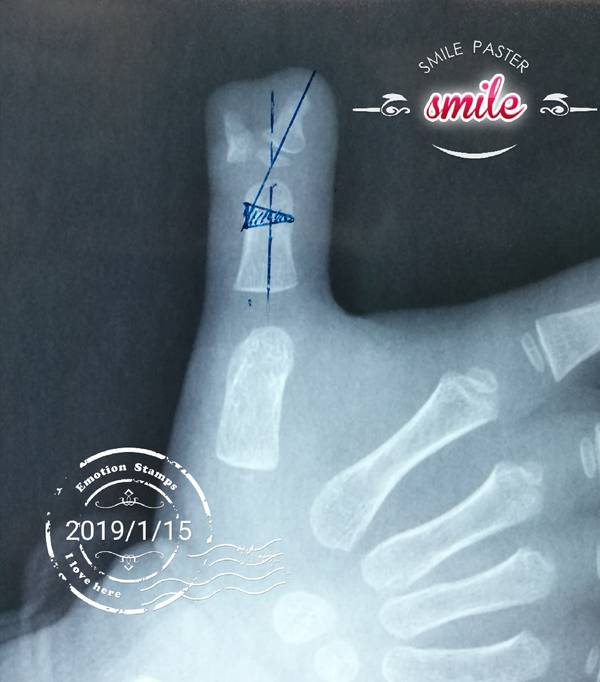

桡侧多指切除截骨矫形术